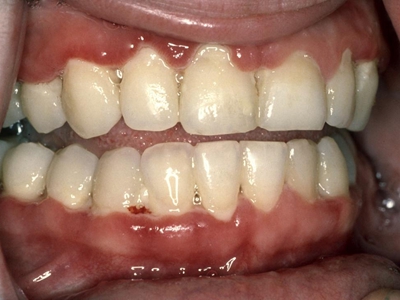

急性坏死性溃疡性龈炎起病急,病程短,常为数天至1-2周,以龈乳头和龈缘的坏死为其特征性损害,尤以下前牙多见,初起时龈乳头充血水肿,个别龈乳头顶端可发生坏死性溃疡,上覆有灰白色坏死物,中央凹下如火山口状。龈缘如虫蚀状,坏死区出现灰褐色假膜,擦去后可见出血创面。龈乳头被破坏后与龈缘成一直线,如刀切状。病损一般不波及附着龈,患处牙龈极易出血,疼痛明显并有腐败性口臭。

重症患者可有低热、疲乏等全身症状,并可伴有下颌下淋巴结肿大和压痛。有的患者可能进展为坏死性龈口炎、坏死性溃疡性牙周炎等疾病,从而导致牙周袋形成、牙槽骨吸收和牙齿松动。